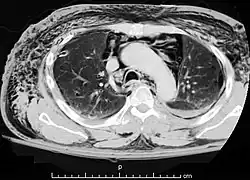

A CT scan showing air in the mediastinum |

Pneumomediastinum (from Greek pneuma – "air", also known as mediastinal emphysema)[1] is pneumatosis (abnormal presence of air or other gas) in the mediastinum, the central part of the chest cavity. First described in 1819 by René Laennec,[2][3] the condition can result from physical trauma or other situations that lead to air escaping from the lungs, airways, or bowel into the chest cavity. In underwater divers it is usually the result of pulmonary barotrauma.[1]